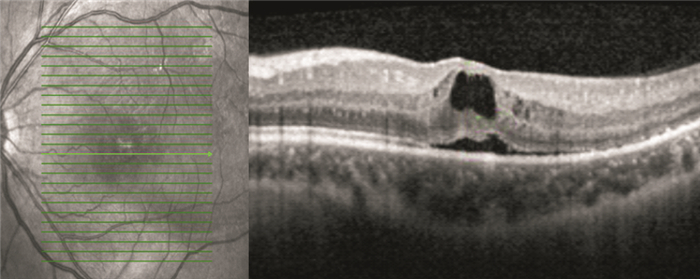

OCT檢查發現,手術后視網膜下液吸收時間1~13個月,平均視網膜下液吸收時間(7.82±3.52)個月。手術后12個月,42只眼中,視網膜下液吸收37只眼,占88.1%;視網膜下液殘留5只眼,占11.9%。視網膜下液吸收37只眼中,視網膜微結構正常15只眼;神經上皮層黃斑囊樣水腫5只眼(圖 1);光感受器內外節連接(IS/OS)斷裂12只眼;IS/OS和外界膜(ELM)斷裂5只眼(圖 2)。

患眼OCT像。神經上皮層黃斑囊樣水腫

患眼OCT像。神經上皮層黃斑囊樣水腫

OCT檢查發現,手術后視網膜下液吸收時間1~13個月,平均視網膜下液吸收時間(7.82±3.52)個月。手術后12個月,42只眼中,視網膜下液吸收37只眼,占88.1%;視網膜下液殘留5只眼,占11.9%。視網膜下液吸收37只眼中,視網膜微結構正常15只眼;神經上皮層黃斑囊樣水腫5只眼(圖 1);光感受器內外節連接(IS/OS)斷裂12只眼;IS/OS和外界膜(ELM)斷裂5只眼(圖 2)。

患眼OCT像。神經上皮層黃斑囊樣水腫

患眼OCT像。神經上皮層黃斑囊樣水腫